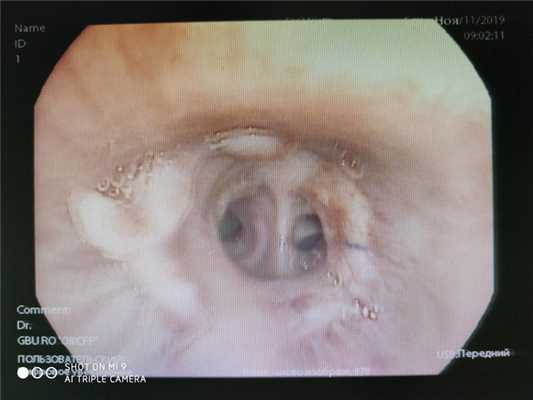

Национальный Центр Онкологии и Гематологии МЗКР. Левое бронхиальное дерево: начиная от средней трети верхнедолевого бронха до устья сегментарных бронхов верхней зоны по медиальной поверхности визуализируется инородное тело желтого цвета, размером 1.0х3.0 см в d, обтурирующее на 2/3 просвет сегментарных бронхов S1,2,3 далее для аппарата не проходим, устья S4,5 проходима. При инструментальной пальпации ткань мягко-эластичная. Половина инородного тела удалена. Отправлена на гистологию, цитологию. Заключение: вероятнее всего грибковое поражение верхнедолевого бронха слева. Врач- эндоскопист: Жакыпов Талантбек Курманбекович

Министерство здравоохранения Кыргызской Республики Национальный центр Онкологии и Гематологии Голосовая щель смыкается симметрично, свободно проходима. При введении аппарата в трахею с/з по задне-левой стенке обнаружен свищевой ход размером 1.3х1.0 см в d, при входе устье видны просвет пищевода, проксимальный конец СРМС стента. Карина утолщенная из-за отека, долевые бронхи ярко-красная, отечная в просвете в большом количестве слизисто-гнойное отделяемое c резким зловонным запахом, вязкая при санации. На задней стенке с/3 трахеи отмечается свищевое отверстие размером около 1.0х1.1 см, на дне которого визуализируется СРМС. Стент полностью закрывает свищевое отверстие. Заключение: Трахео-пищеводный свищ. Гнойный эндобронхит. Состояние после стентирования пищевода. Эндоскопист: Жакыпов Т.К.